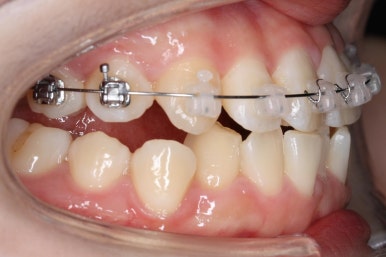

연산동교정치과에서 이번에 진행한 방법은 비발치교정이기 때문에 미니스크류를 잇몸뼈에 식립합니다.

위 사진에서 화살표 부분이 미니스크류인데요.

어금니쪽 잇몸에 아주 작은 나사가 보이실텐데요. 이것을 이용해서 전체 치열을 뒤로 당겨넣습니다. 물론 사랑니는 제거가 된 상태입니다.

아랫니도 어느 정도 많이 가지런해졌습니다.

윗니를 계속 당겨 넣습니다.